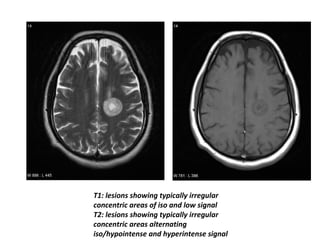

– T1: lesions are typically irregular concentric areas of

iso and low signal

– T2: lesions are typically irregular concentric areas

alternating iso/hypointense and hyperintense signal

T1: lesions showing typically irregular

concentric areas of iso and low signal

T2: lesions showing typically irregular

concentric areas alternating

iso/hypointense and hyperintense signal